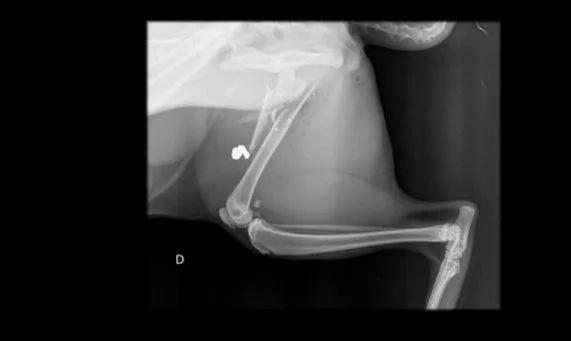

DISTRITO FEDERAL | Um gato foi atingido na perna por uma bala perdida na última sexta-feira (17) no condomínio Solar da Serra, no Lago Sul, em Brasília. O animal teve o fêmur fraturado. A investigação é conduzida pela 6ª DP.